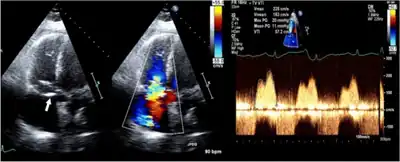

Ultrasound image; 2D and color Doppler in an individual with anti-phospholipid antibody syndrome shows thickening of valve leaflets and continuous-wave Doppler with a mean pressure gradient of 11 mmHg, consistent with severe tricuspid stenosis

A rumbling mid-diastolic murmur can be heard during auscultation caused by the blood flow through the stenotic valve.[2] It is best heard over the left sternal border.[2] A tricuspid opening snap may be heard,[2] with wide-splitting S2. It may increase in intensity with inspiration (Carvallo's sign).

Tests include chest X-ray and ECG.[2] Diagnosis is confirmed by an echocardiograph, which will also allow the physician to assess its severity.[2]